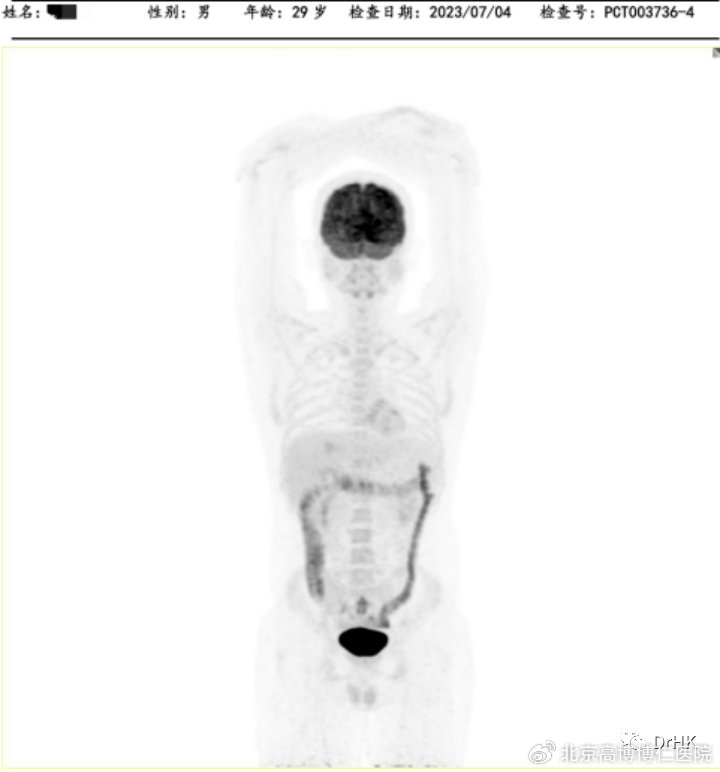

2022-04-02开始,DA-TEDDi-R方案联合靶向(奥布替尼+利妥昔单抗+地米+脂质体多柔比星+依托泊苷+替莫唑胺+长效GCS+鞘注Ara-C)治疗×2周期后,PET-CT评效代谢性完全缓解(患病以来首次达到完全缓解):弥漫大 B 细胞淋巴瘤,Deauville 评分2-3分,与本中心2022-4-1PET/CT 显像比较:原肝脏累及病灶明显减小、高代谢消失;原左侧臀大肌累及病灶消失;全身多发骨(双侧肩胛骨、锁骨、肋骨、胸骨、骨盆骨、脊椎骨)局部骨质吸收、破坏改变,部分区域骨质密度增高,以左侧髂骨为著,髓腔葡萄糖代谢弥漫增高,考虑治疗后反应性改变为主,请结合骨髓穿刺检查。

随后患者定期随访,分别于移植后半年、一年完善影像学评估,令人欣慰的是患者目前一直保持完全缓解状态。PET如下图所示:

(移植后一年影像学评估)